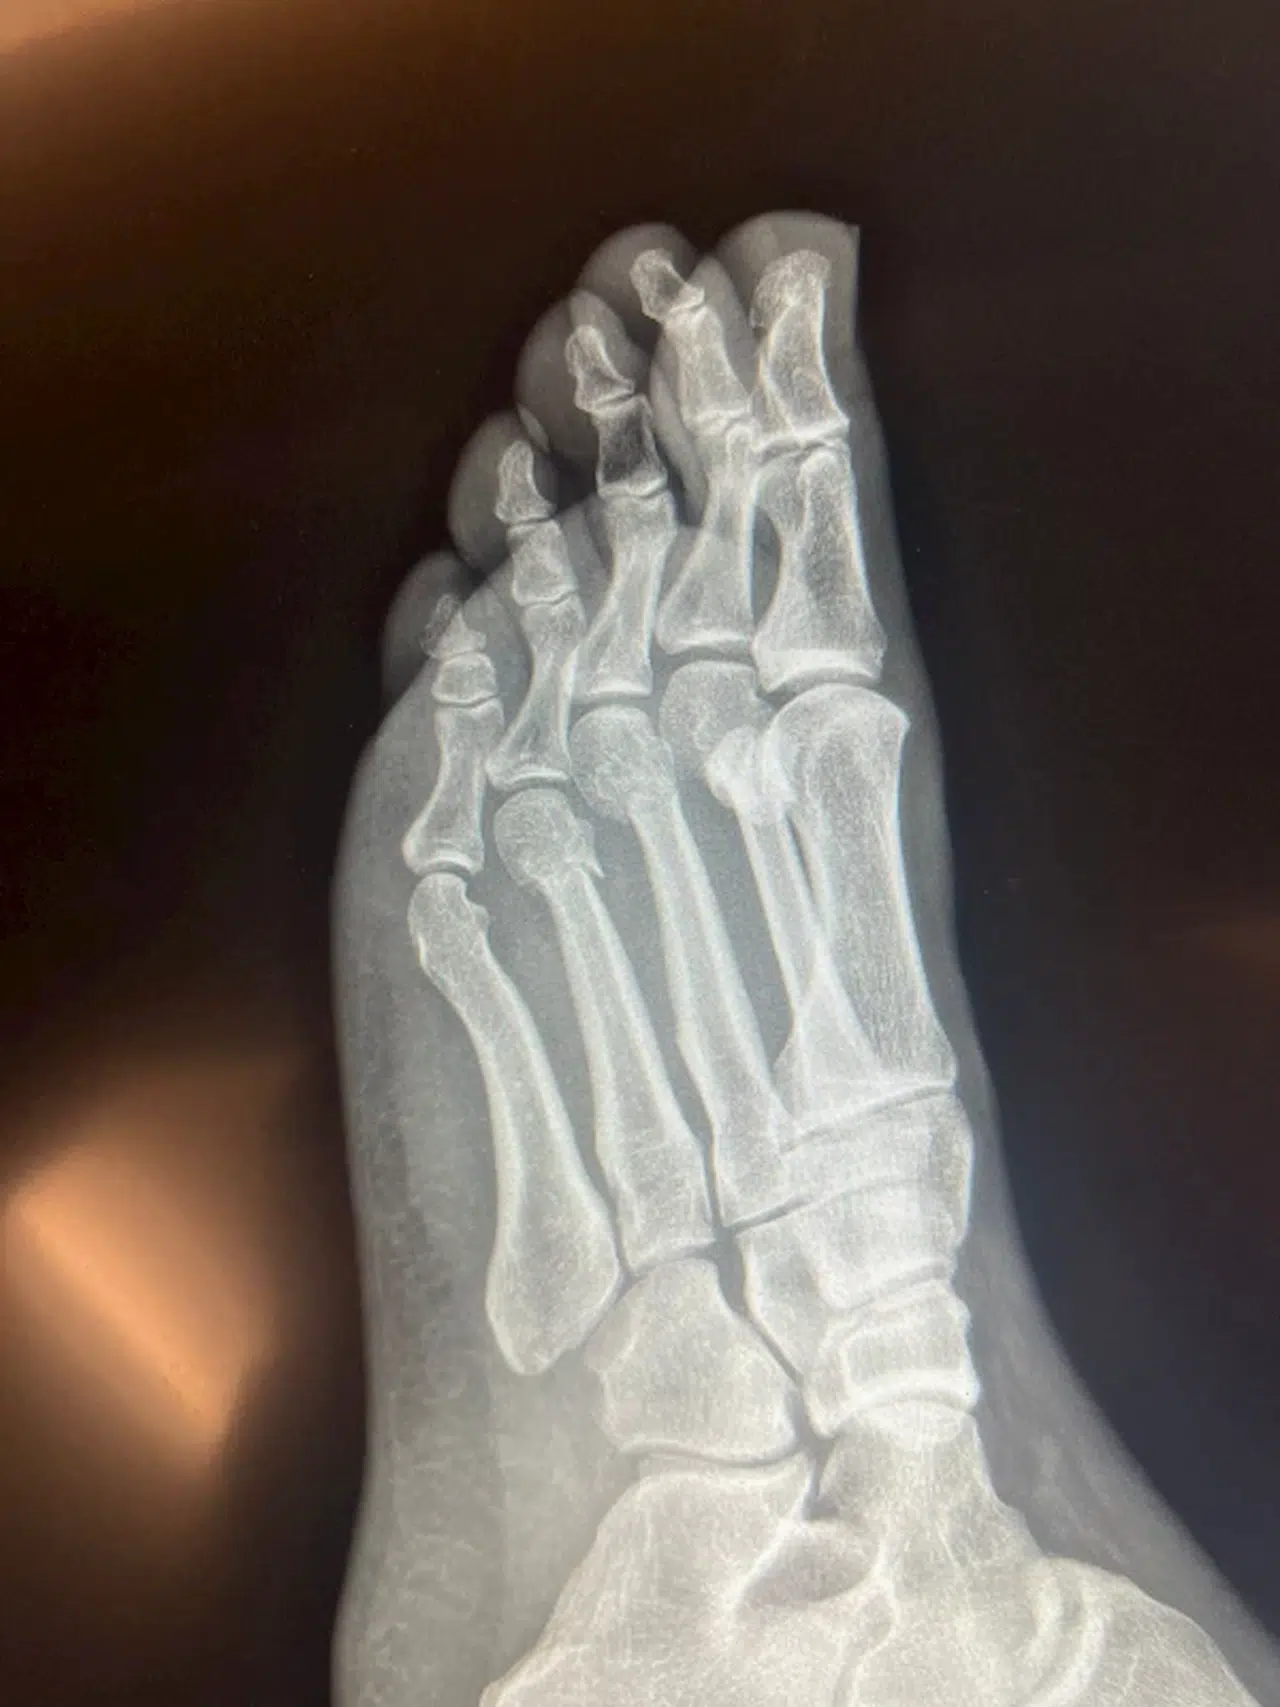

Özgür Özel'den, 'ayağından vuruldu' iddialarına röntgenli yanıt

Aliekber METE/ANKARA, (DHA)- CHP Genel Başkanı Özgür Özel, 'ayağından vuruldu' yönündeki iddialara röntgen filmlerini paylaşarak yanıt verdi.

CHP Genel Başkanı Özgür Özel'in geçen hafta evinde geçirdiği kaza sonucunda ayağında kırıklar meydana gelmişti. Kazanın duyulmasının ardından bazı sosyal medya hesaplarında, Özgür Özel'in ayağından vurulduğu iddia edildi. Tartışmaların sürmesi üzerine Özel, ayağının röntgen filmlerini paylaştı. (DHA)